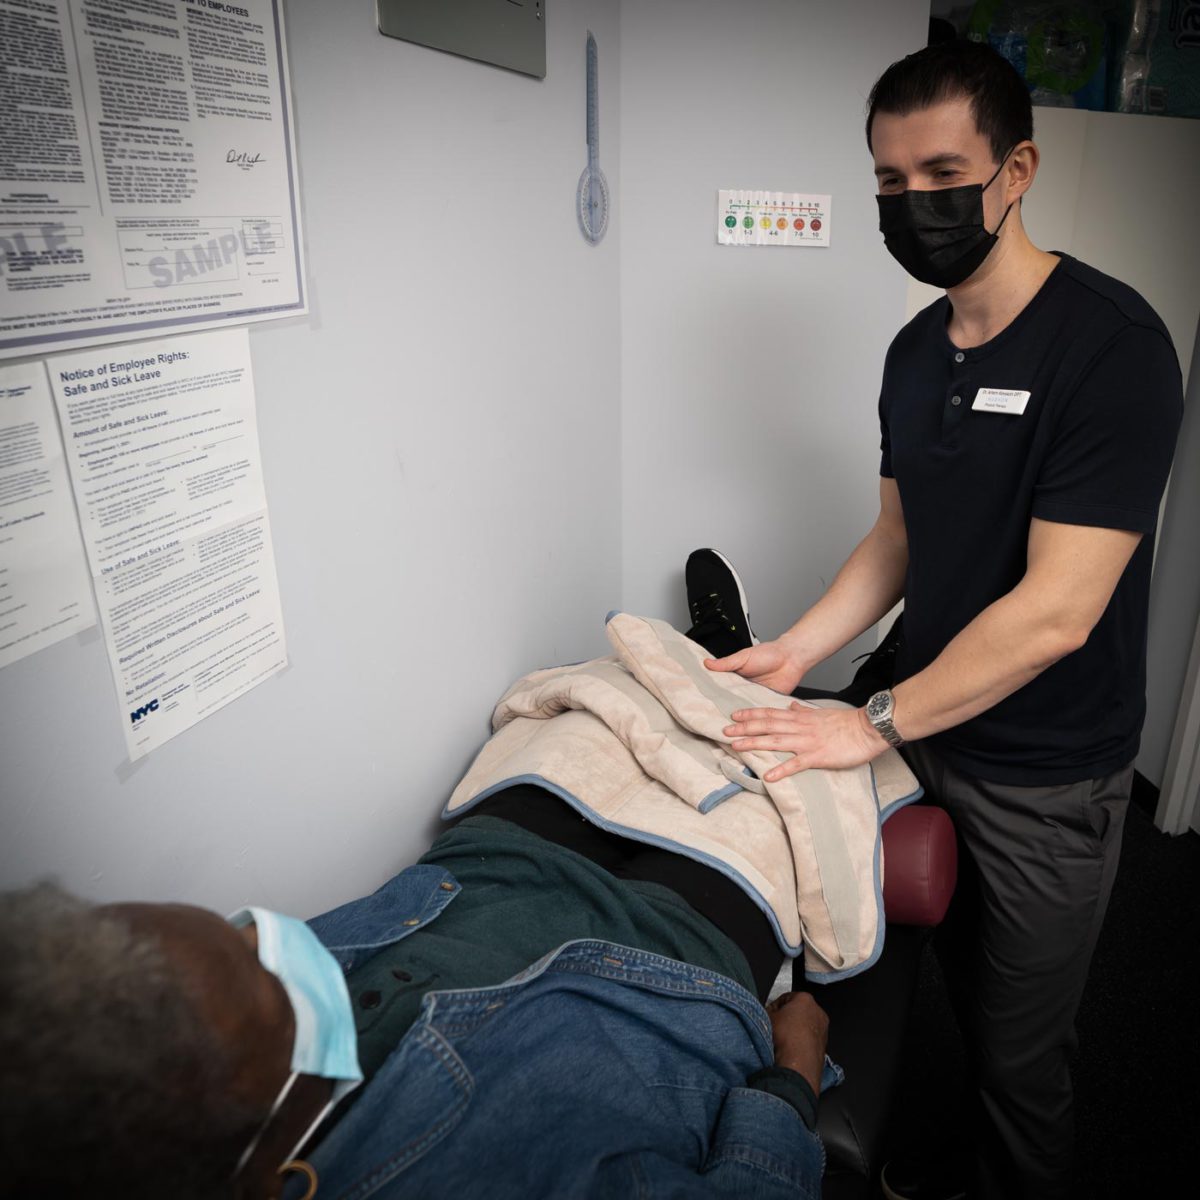

CRYO- AND HEAT THERAPY

Physical Therapists routinely use both cryotherapy and heat therapy in the clinic to treat a wide range of conditions. These conditions range from acute tissue injuries, such as muscle and joint sprains, myofascial trigger point release, tendinitis, acute localized swelling after injuries, bursitis, and many more.